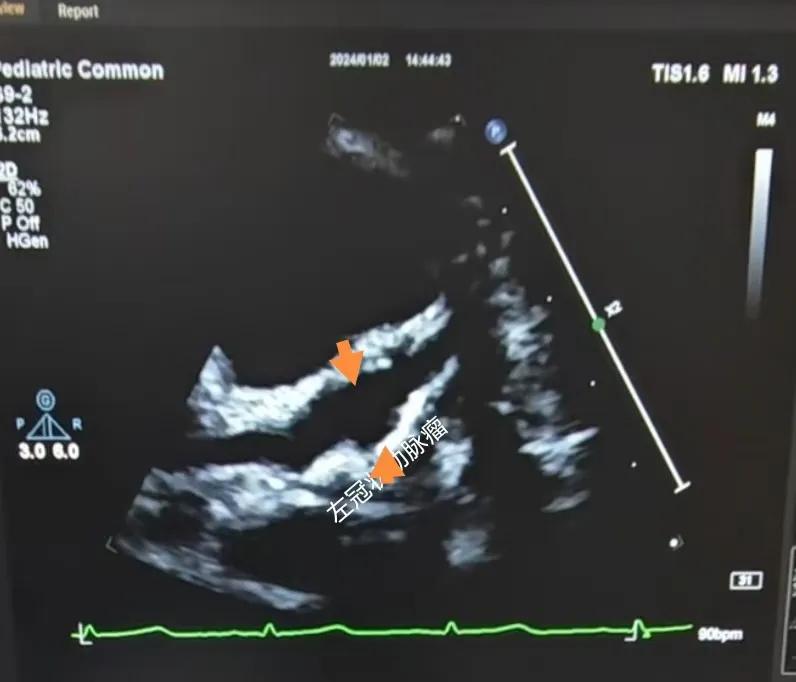

(川崎病患兒:增寬的右側(cè)冠狀動(dòng)脈)

(川崎病患兒:左冠狀動(dòng)脈瘤)